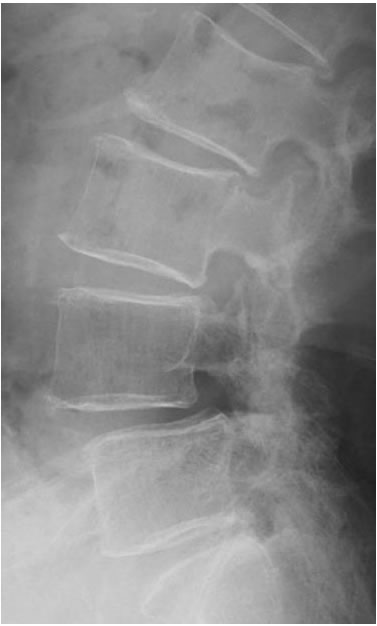

不安定性を擁している 腰椎すべり症のレントゲン